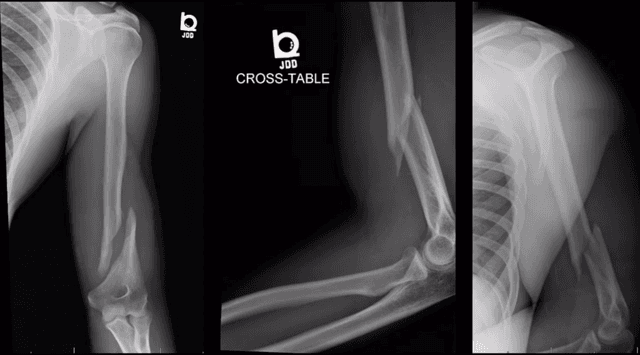

Imaging

Pre-op